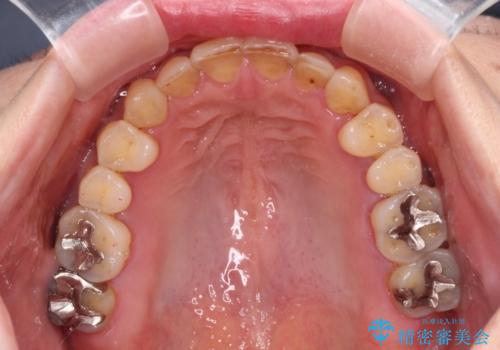

- 歯列不正と、どこで咬んで良いのか分からない咬み合わせを気にして来院された患者様です。

下顎骨は左側にシフトしており、咬み合ったときには奥歯と前歯の一部しか接触していない状態でした。

骨格的な左右差は歯列矯正は改善できないため、上下歯列が全体的に接触することをゴールとしてインビザラインにて矯正治療を行うこととしました。